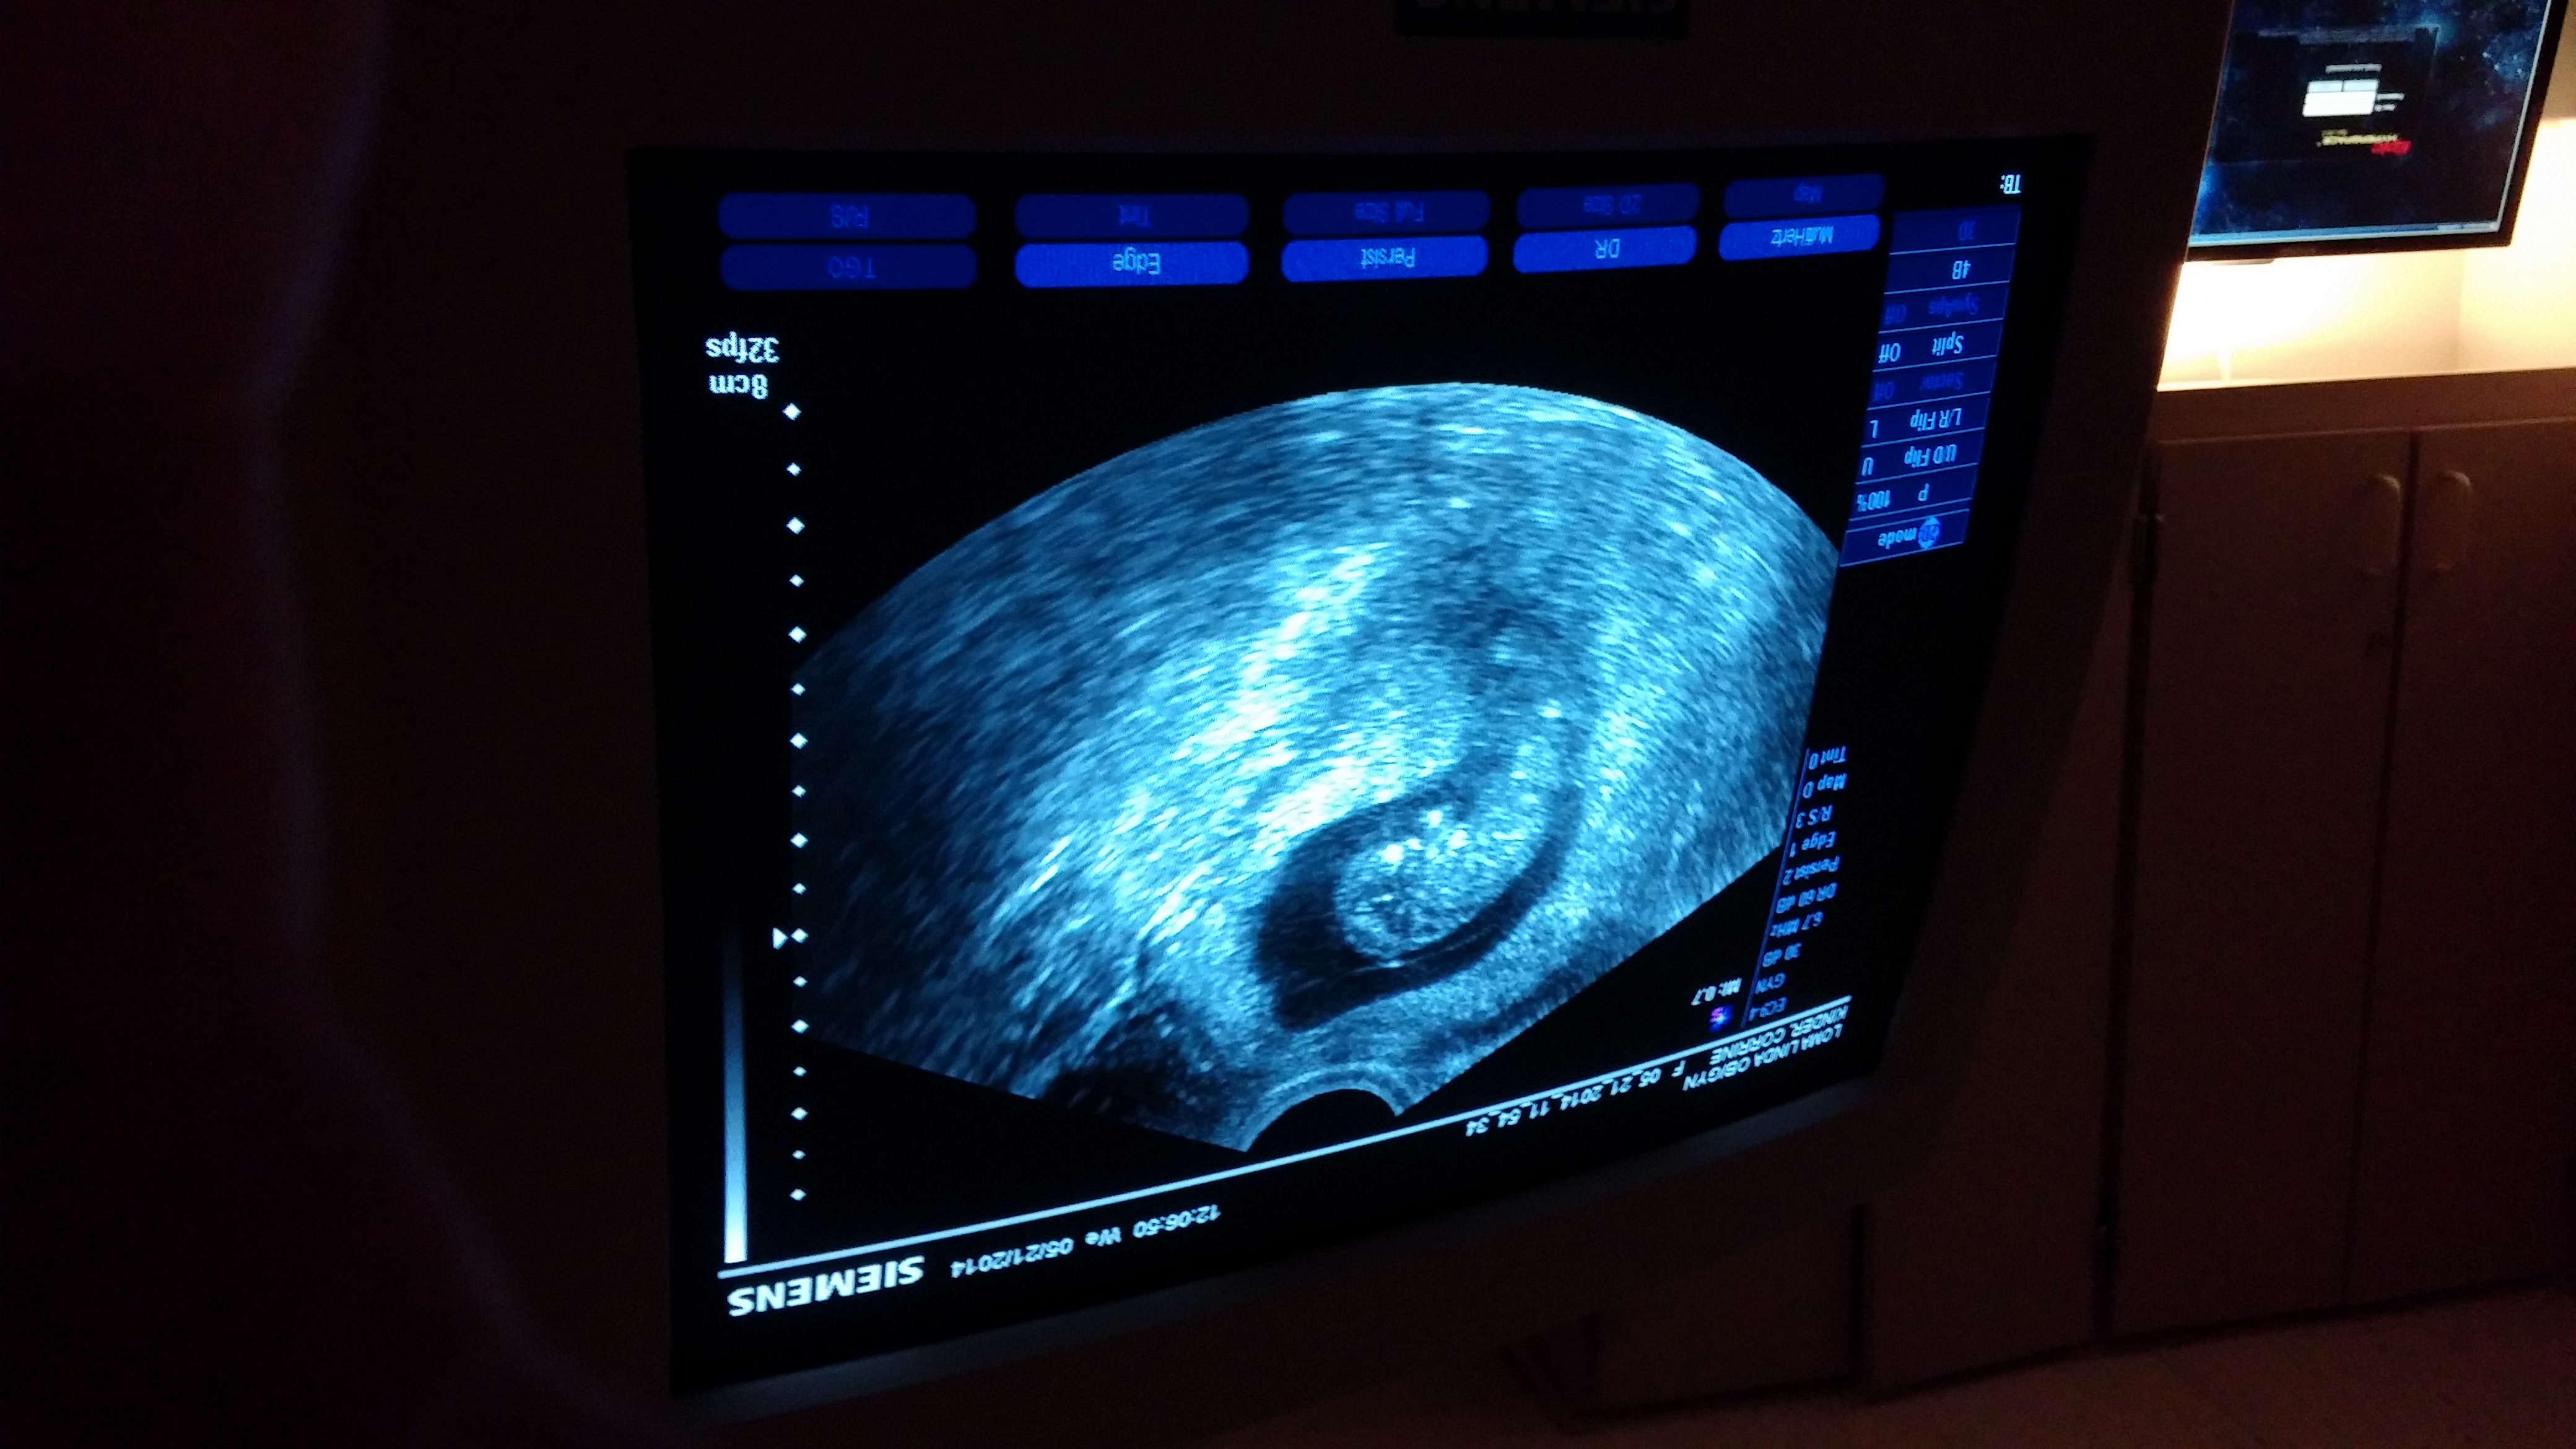

Well, everyone knows what this means!!! I saw my baby and their adorable 160bpm heart beat on my ultrasound today!!!

I will post the pics and video when i get to a computer.

I have another ultrasound on the 2nd, we will get an accurate due date then